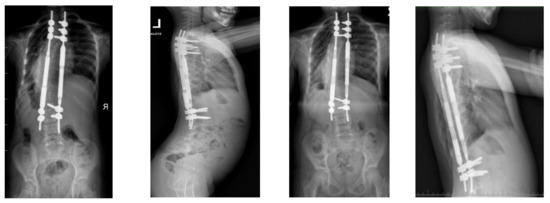

No deep infections were observed during follow-up. At follow-up after 4.5 years, we observed a loss of distraction without other known radiological signs mentioned in the literature (Figure 7).

Figure 7.

X-rays at follow-up after 1 year (left AP and LAT) and at follow-up after 4.5 years (right AP and LAT) before revision surgery for MCGR replacement.

We decided to replace the 4.5 MCGR with a 5.5 MCGR. We performed revision surgery to replace the screws and MCGRs in January 2022 (Figure 8).

Figure 8.

X-rays at 5-year follow-up, after revision surgery for MCGR replacement.